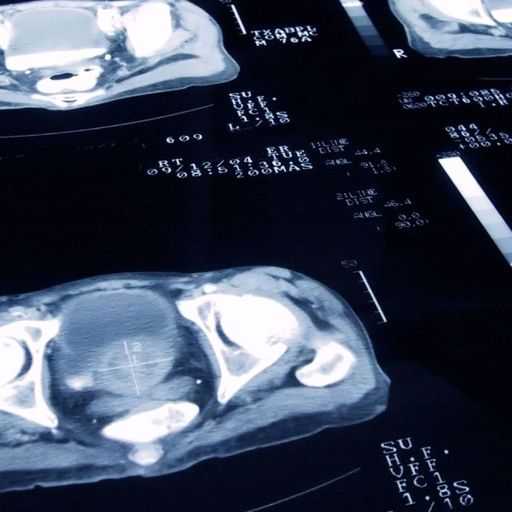

I then had a couple more tests to compare PSA levels, followed by a biopsy and then a magnetic resonance imaging scan (MRI) to confirm the diagnosis.